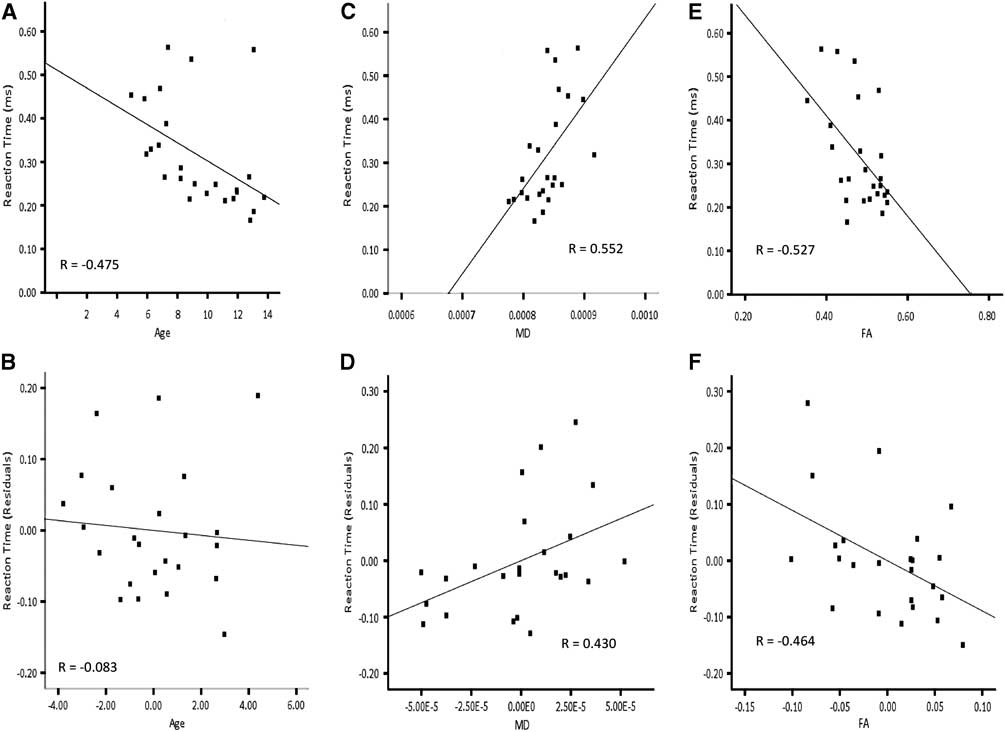

Based on higher-order regression analysis, the structure of the cortico-spinal tracts in the left hemisphere, the inferior fronto-occipital fasciculus in the right hemisphere and the optic radiations bilaterally showed age-related changes, and also predicted reaction time. Hence, these connections were included in the final model predicting right hand reaction time. The linear term for age was included in the hierarchical model. The linear terms for FA of the cortico-spinal tract of the left hemisphere, MD of the inferior fronto-occipital fasciculus of the right hemisphere, MD of the optic radiations in the right hemisphere and the quadratic term for MD of the optic radiations in the left hemisphere were included together in a stepwise manner. AD of the optic radiation in the right hemisphere was not carried forward to the primary analyses to avoid collinearity with MD. Age accounted for a significant amount of the variance observed for reaction time of the right hand when entered into the regression model first (Table 4a; Model 1:1). Adding FA of the cortico-spinal tract in the left hemisphere and MD of the inferior fronto-occipital fasciculus of the right hemisphere to the model in a stepwise manner significantly increased the amount of predicted variance in reaction time by approximately 26%. Conversely, there was no significant increment in predicted variance when age was entered into the model after FA of the cortico-spinal tract in the left hemisphere and MD of the inferior fronto-occipital fasciculus of the right hemisphere (Table 4a; Model 1:2). The striking relation between age and reaction time of the right hand was no longer apparent after accounting for FA of the cortico-spinal tract in the left hemisphere and MD of the inferior fronto-occipital fasciculus in the right hemisphere (Figure 5). On the other hand, the relation between reaction time of the right hand and FA of the cortico-spinal tract in the left hemisphere remained evident after accounting for age and MD of the inferior fronto-occipital fasciculus in the right hemisphere. Moreover, the correlation between reaction time of the right hand and MD of the inferior fronto-occipital fasciculus in the right hemisphere was still apparent after accounting for age and FA of the cortico-spinal tract in the left hemisphere. DTI indices from the optic radiations did not contribute unique variance and were not maintained in either model.

Fig. 5 Correlations for right hand reaction time and residuals as a function of age, MD of the right inferior fronto-occipital fasciculus and FA of the left cortico-spinal tract. Note that the correlation between age and reaction time (A) is not apparent in after accounting for MD of the right inferior fronto-occipital fasciculus and FA of the left cortico-spinal tract (B). The correlation between MD of the right inferior fronto-occipital fasciculus and reaction time (C) remains after accounting for age and FA of the left cortico-spinal tract (D). The correlation between FA of the left cortico-spinal tract and reaction time (E) is still evident after accounting for age and MD of the right inferior fronto-occipital fasciculus (F).

Because of the curvilinear relation between age and reaction time of the left hand, the quadratic term for age was included in the final model predicting left hand reaction time. Furthermore, MD of the optic radiations and CST in the right hemisphere were included in a stepwise manner, considering the age-related changes in these tracts and that they predicted left hand reaction time. RD of the optic radiation in the right hemisphere was not included in the primary analyses to avoid collinearity with MD. Neither age nor MD of the optic radiation accounted for unique variance of left hand reaction time when the other was included in the model (Table 4b; Model 2). The fact that age and MD together account for so much variability in reaction time, but so little unique variability, suggests that the impact of these two variables on reaction time is difficult to separate statistically. MD of the right CST did not contribute unique variance and was not maintained in either model.